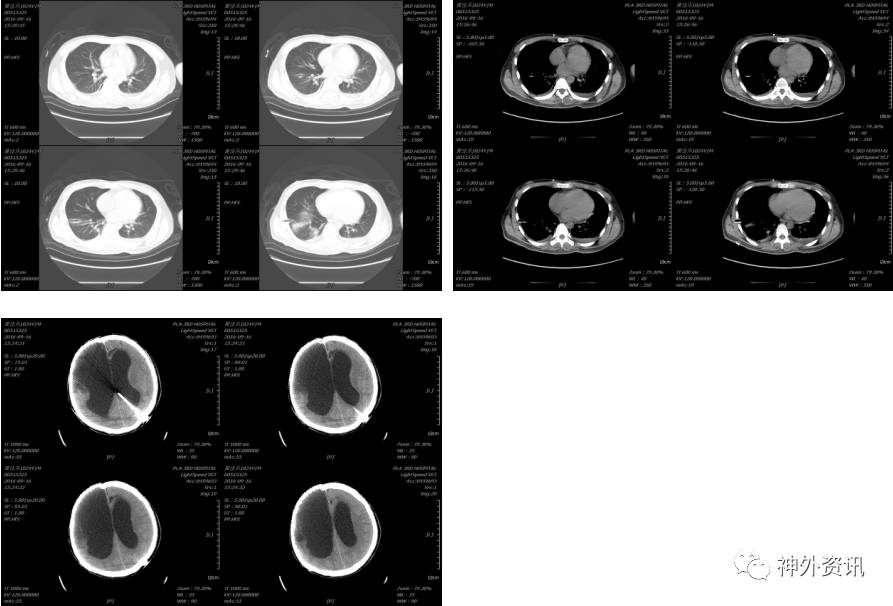

2016-09-30患者再次出现出现咳嗽,发热38.6度,血常规:白细胞(WBC)21.78×109/L,中性细胞比率(NE%)88.4%,继续给予舒普深等药物, 2016-10-04血常规:白细胞(WBC)8.40×109/L、中性细胞比率(NE%)66.5%,复查胸部CT示:

患者于2016-10-06体温恢复正常,于2016-10-08停用舒普深、痰热清,分流储液囊中脑脊液:无色透明脑脊液,葡萄糖2.83mmol/L,细胞数130×106/L,2016-10-10出现发热,分流管处皮下水肿,沿分流管皮肤变红,给予舒普深,2016-10-10头部分流泵处出现皮下包块,沿分流管皮肤变红,大约10多分钟后皮肤变成正常肤色。

2016-10-15复查头颅CT示:拔出引流管后未见脑室继续扩大。

胸部情况较前明显好转,于2016-12-01再次复查头颅CT示未见脑室进一步扩大。

后患者逐渐康复,未再行脑室腹腔分流术,耐受良好,于2017年3月复查头颅CT未见脑室明显扩大,意识清楚,言语清晰,对答切题,扶物下可自主行走,生活大部分基本自理。

2017-03-30头颅CT示: